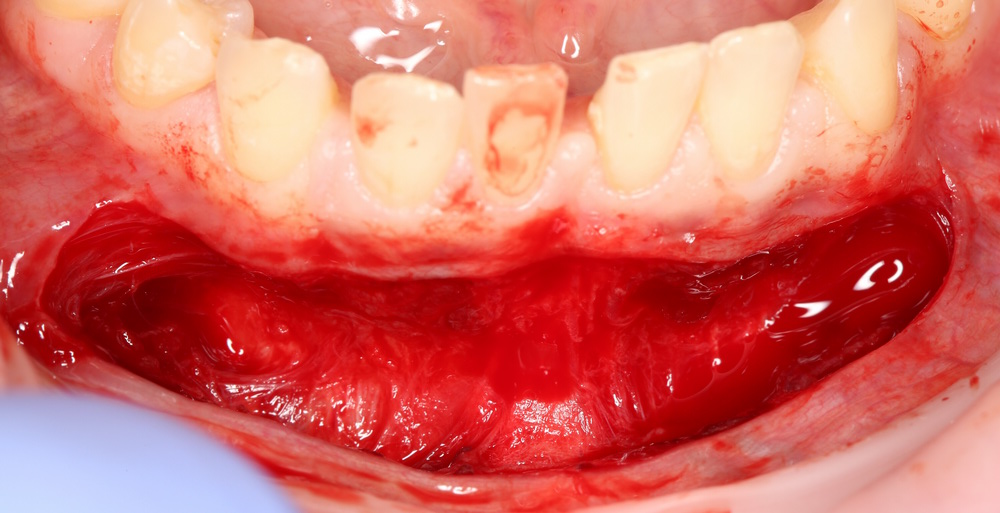

Разрез в преддверии полости рта, на 1-2 мм ниже переходной складки:

Тупым способом отслаиваются мягкие ткани до надкостницы. Ее очень легко определить — она, в отличие от других слоев, она неподвижно прикреплена к кости. Таким образом, создается ложе под матрицу Mucograft: